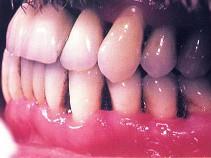

问题 水平型食物嵌塞的原因()

选项 A.牙龈萎缩 B.充填式牙尖 C.相邻牙边缘嵴不在同一水平面 D.充填物悬突 E.邻牙触点丧失

答案 A